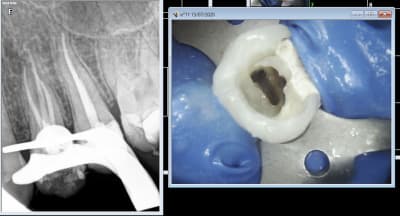

Comparaison des traitements de 2 praticiens différents au même tarif. Même patient 16 26. Pourquoi se faire chier aucun souci sur 26. ,

> Comparaison des traitements de 2 praticiens différents au même tarif. Même

> patient 16 26. Pourquoi se faire chier aucun souci sur 26. ,

> c est terrible parce que selon Gabzou... le gars qui a foiré l endo 26 a fait

> exprès puisque c est facile...

En plus t'u m'enlèves mes loupes fois 5 mon miroir soufflant et quelques autres astuces pour bosser seul en vision indirecte ( Mon unique assistante n'a pas que ça à foutre à tenir l'aspi elle est plus utile ailleurs ) pour faire une endo difficile d'accès en vision directe c'est pas la même messe.

Indépendamment du reste, il y a clairement une racine MV non traitée dont on distingue le canal, ce qui est l'anatomie standard d'une 26.

Conclusion, le praticien l'a sciemment ignorée pour aller plus vite.

On peut discuter de la rémunération, des raisons qui ont amené ce praticien à choisir de bâcler le travail, mais il est indiscutable que le praticien ne peut pas avoir ignoré avoir fait n'importe quoi.

J'ai bien précisé que tout n'est pas facile. Cette 26 l'est, je n'ai quasiment aucun doute.